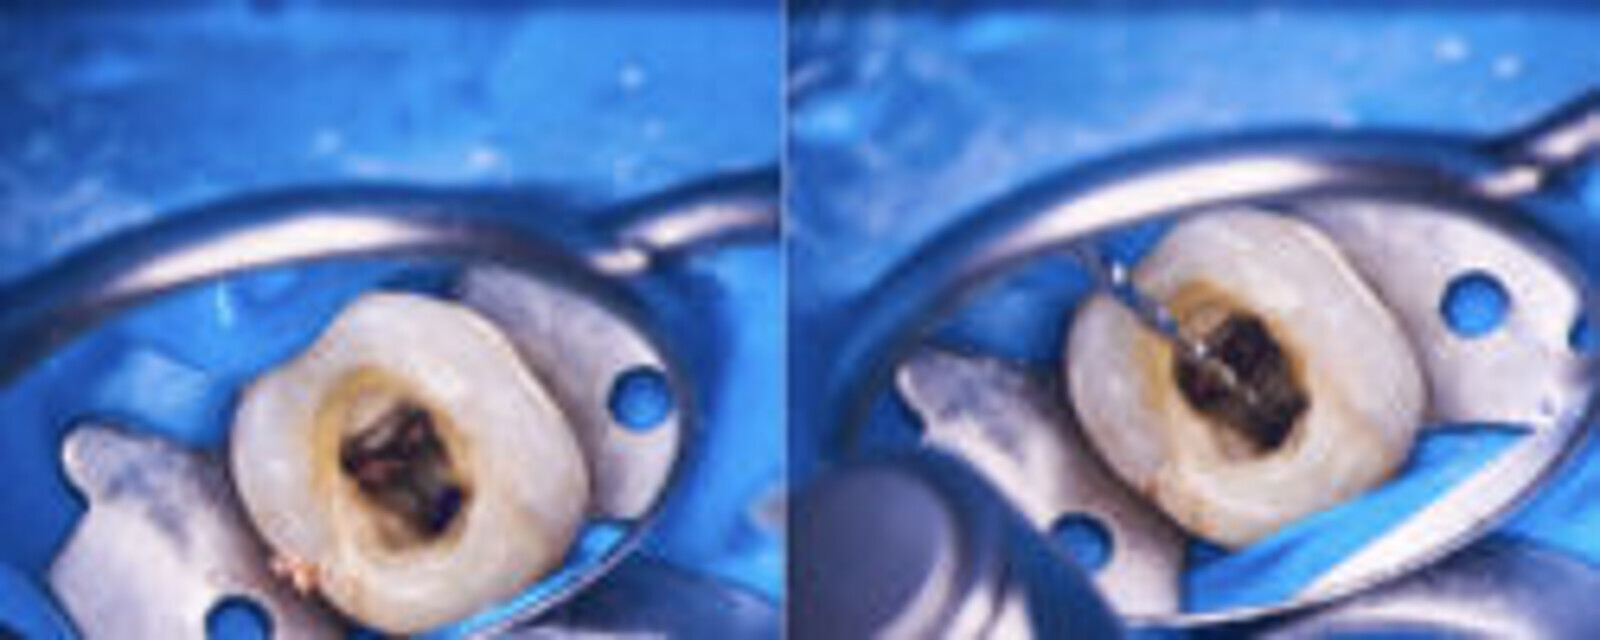

Klinički, uočen je značajan gubitak strukture zuba. Pacijentkinja je informisana o složenosti procedure i procentu uspešnosti, što je prihvatila i odlučila da sprovede tretman. Nakon davanja anestezije stavljen je koferdam na zub 46. Na osnovu CBCT snimka dezinfikovana su dva radna polja primenom hipohlorita. Na osnovu rezultata CBCT pregleda uočeno je postojanje dve perforacije, mezijallno i distalno. Nakon stavljanja kolagene membrane u perforacije radi kreiranja podloge za biokeramiku, stavljen je Biodentine (Septodont). Ovaj materijal je izabran zbog fantastičnih karakteristika primene i kratkog vremena sleganja što je najvažnije prilikom izvođenja tretmana tokom jedne posete. Biodentine (Septodont) pripremljen je u skladu sa uputstvom za upotrebu i stavljen na lokalitet. Cement je blago kondenzovan i oblikovan pomoću papirnih poena.

SLIKA 2